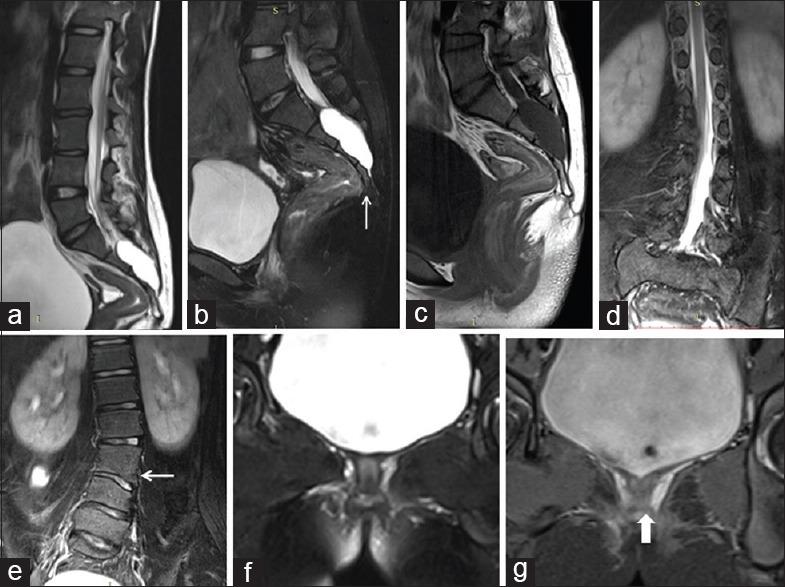

In our study, 21 pediatric patients were diagnosed with sacral agenesis/dysgenesis related to CRS. According to the Pang's classification, 2 (9.5%) patients were Type I, 5 (23.8%) patients were Type III, 7 (33.3%) patients were Type IV, and 7 (33.3%) patients were of Type V CRS. Clinically, 17 (81%) patients presented with urinary incontinence, 6 (28.6%) with fecal incontinence, 9 patients (42.9%) had poor gluteal musculatures and shallow intergluteal cleft, 7 (33.3%) patients had associated subcutaneous mass over spine, and 6 (28.6%) patients presented with distal leg muscle atrophy. MRI showed wedge-shaped conus termination in 5 (23.8%) patients and bulbous conus termination in 3 (14.3%) patients above the L1 vertebral level falling into Group 1 CRS while 7 (33.3%) patients had tethered cord and 6 (28.6%) patients had stretched conus falling into Group 2 CRS.

在我们的研究中,21例小儿患者被诊断为与CRS相关的骶骨发育不全/发育异常。根据庞氏分类,2例(9.5%)患者为I型,5例(23.8%)患者为III型,7例(33.3%)患者为IV型,7例(33.3%)患者为V型CRS。临床上,17例(81%)患者出现尿失禁,6例(28.6%)出现大便失禁,9例(42.9%)患者臀肌发育不良且臀间裂浅,7例(33.3%)患者脊柱上方有皮下肿块,6例(28.6%)患者出现小腿远端肌肉萎缩。MRI显示,5例(23.8%)患者在L1椎体水平以上出现楔形圆锥终丝,3例(14.3%)患者出现球茎状圆锥终丝,属于1组CRS;7例(33.3%)患者有脊髓栓系,6例(28.6%)患者有圆锥拉长,属于2组CRS。